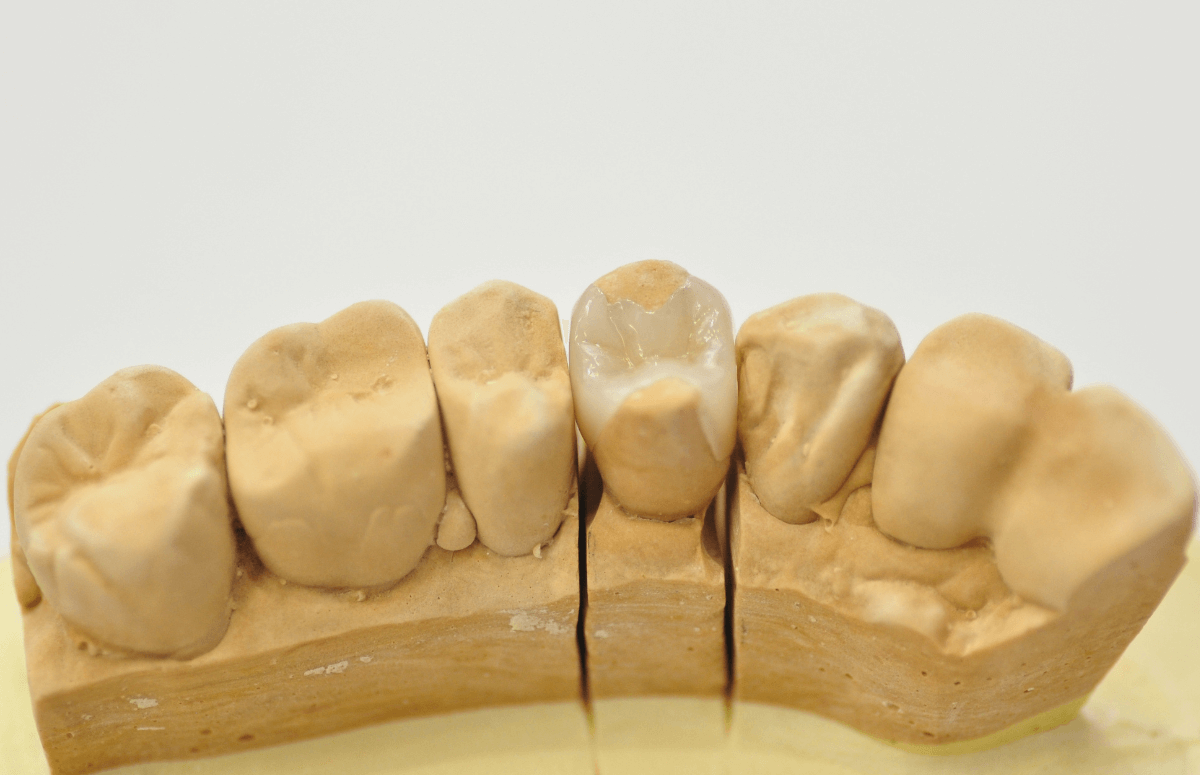

模型上で精密に製作します。

模型上で精密に制作します。

模型上で、ファイバーコアをしっかり製作します。